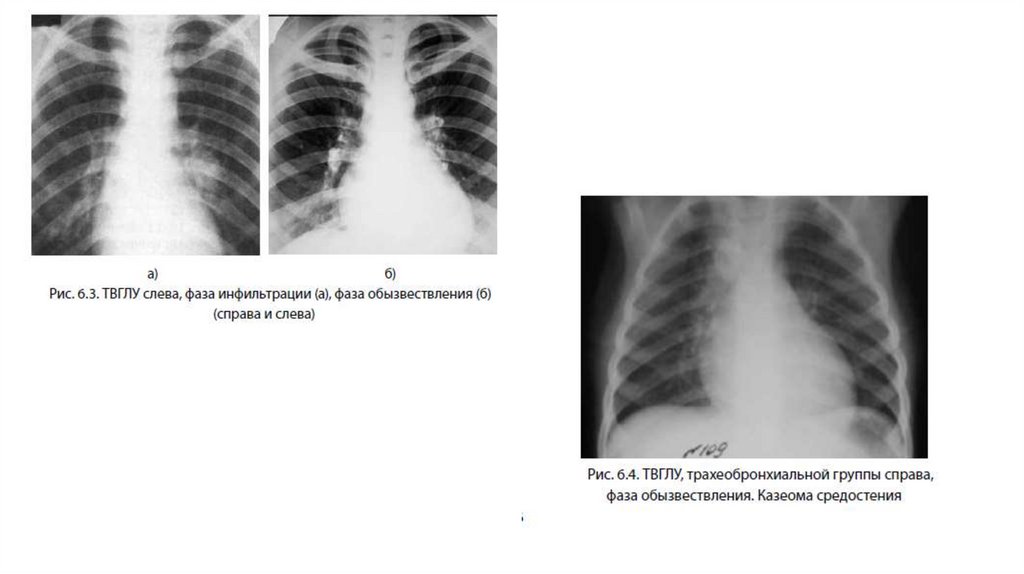

4. Рентгенологически: Наиболее характерным является

одностороннее расширение тени корня легкого или тени

средостения. При лечении постепенно восстанавливаются

размеры и структура корней легких. В некоторых случаях,

особенно при самоизлечении, формируются кальцинаты,

иногда множественные.

5. Для диагностики малых форм ТВГЛУ наиболее

информативным является КТ